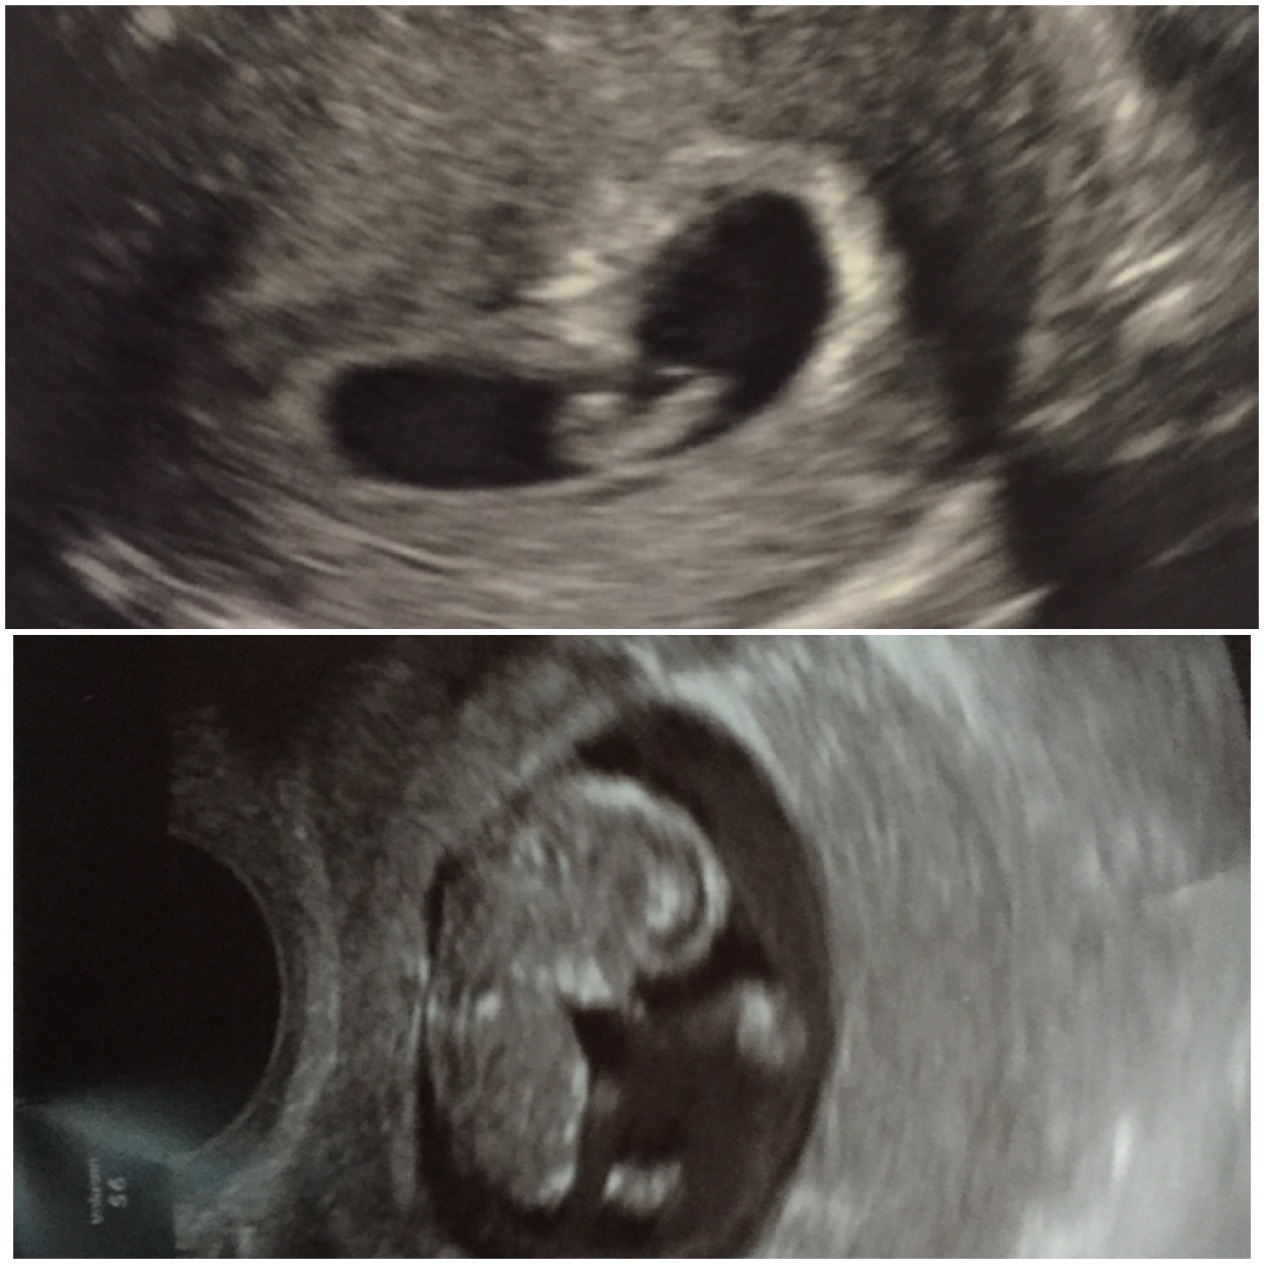

• We had our first ultrasound today at 7w5d after IVF with transfer of ONE embryo.  Imagine our surprise when we saw TWO babies! Identical twins - we are still in shock and yet so excited!  We saw both heartbeats, which was indescribably amazing.  We will have another US on 11/20 (8w6d) before graduating from our RE to our OB.

• @theatremandy - they didn't see a membrane but thought it might still be too early. I'll be getting another scan next week, so I guess we'll know by then! We are nervous but looking forward to the twin adventure! DW is an identical twin herself, so it'll be fun having another set in the family.